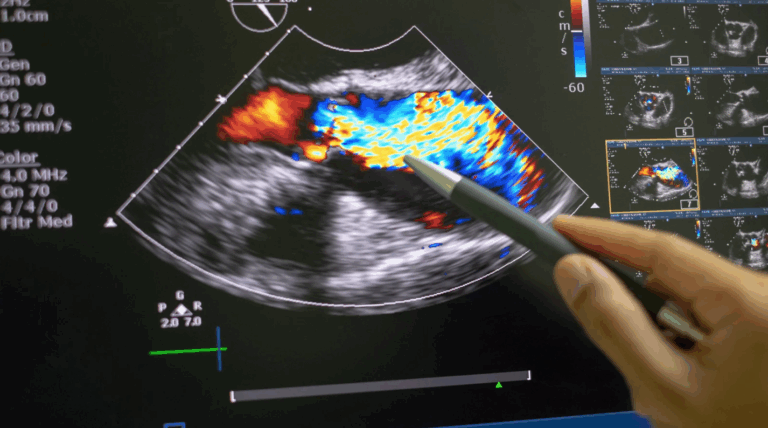

O ecocardiograma com Doppler colorido é um exame de imagem por ultrassonografia que permite visualizar a estrutura do coração e o fluxo do sangue em tempo real. Com ele, é possível detectar anomalias nas válvulas, alterações na contração cardíaca e distúrbios no fluxo sanguíneo.

O modo Doppler adiciona o recurso de analisar o fluxo sanguíneo dentro das cavidades cardíacas, usando cores (geralmente vermelho e azul) para indicar direção e velocidade do sangue.